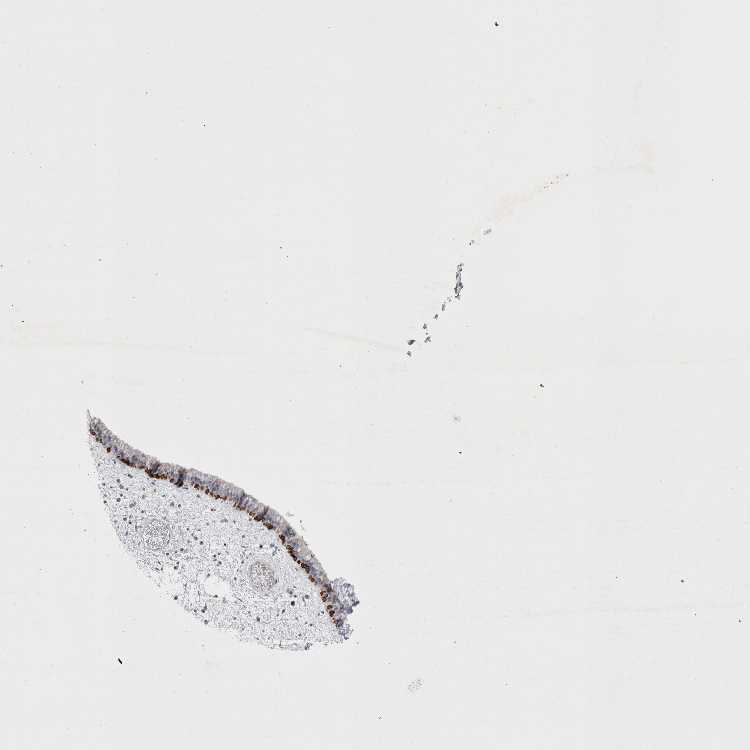

NASOPHARYNX - Antibody stainingi

Antibody staining in the annotated cell types in the current human tissue is reported as not detected, low, medium, or high, based on conventional immunohistochemistry profiling in selected tissues. This score is based on the combination of the staining intensity and fraction of stained cells.

Each image is clickable and will lead to virtual microscopy that enables deeper exploration of all samples and also displays staining intensity scores, fraction scores and subcellular localization as well as patient and tissue information for each sample.

Antibody HPA026970Antibody HPA029126

Respiratory epithelial cells MediumNot detected